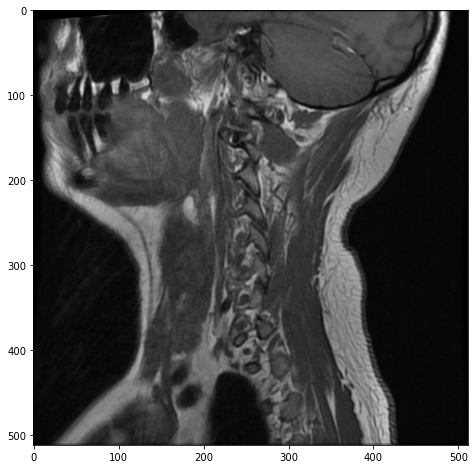

plt.imshow(mri[7, :, :], cmap="gray", aspect="equal")

Voila! Here we can clearly see a patient’s neck from a side view with the spinal cord running up through to the base of the patient’s brain in the top right, and the patient’s front teeth on the left.

This is the 7th slice of 15, so it’s showing us the approximate middle of the patient’s neck. But if we wanted to move outward from the center of the patient’s body, we could pick a slice closer to 0 or 14: